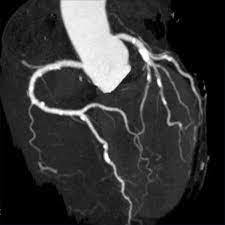

Coro-scanner: sert à quoi ?

. permet de visualiser, après injection, les artères coronaires.